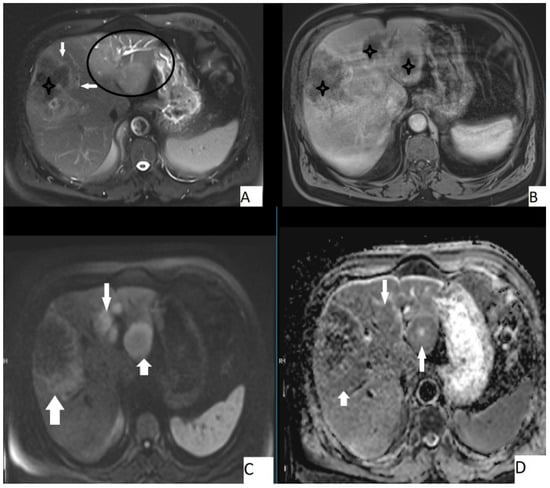

The most frequently encountered MRI pattern was a heterogeneous mass with irregular contours with central necrosis (78.7%). Most of the lesions (85.4%) lacked contrast enhancement (Figure 4). The most frequent types were Kodama type 2 and 3 lesions (42.6% and 48.7%, accordingly). Table 4 details the MRI findings.

Figure 4.

67-year-old male, axial T2WI (A), axial postcontrast T1WI (B), axial DWI (C), and axial ADC map (D). Hepatic lesion with irregular borders (A, arrows) and other hepatic homogeneous T2 hyperintense lesions (A, circle). Central necrosis was present (A,B, stars), no contrast enhancement is seen (B). Lesions were slightly hyperintense on DWI and slightly hypointense on ADC map. Mean ADC value of the large lesion was 1.58 × 10−3 mm2/s, while the smaller ones were 1.44 × 10−3 mm2/s and 1.42 × 10−3 mm2/s.

The mean ADC value of hepatic AE lesions’ solid components was 1.51 ± 0.32 × 10−3 mm2/s (range: 0.97–1.78 × 10−3 mm2/s) (Figure 3). Table 5 summarizes the mean ADC values for the various types of AE lesions.